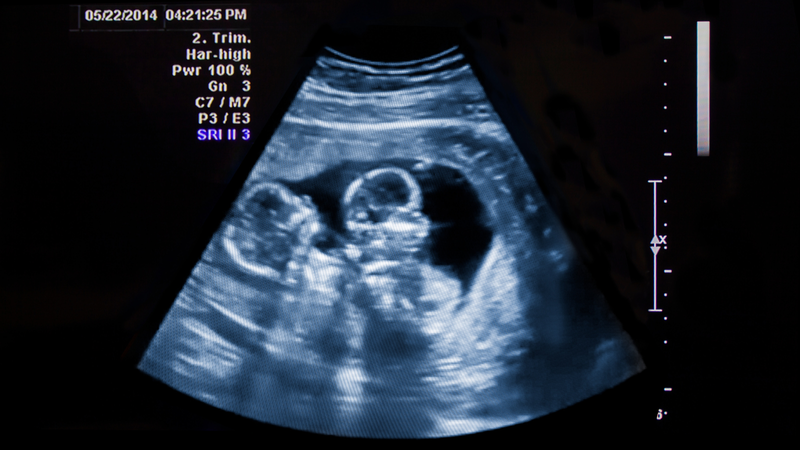

Trong vô vàn điều kỳ diệu của tự nhiên và sinh học, hiện tượng sinh đôi luôn thu hút sự quan tâm đặc biệt. Hình ảnh hai em bé có nhiều nét tương đồng, chào đời cùng một lúc, gợi lên những câu hỏi về cơ chế hình thành. Vậy, sinh đôi thực chất là gì? Quá trình tạo ra một thai kỳ sinh đôi diễn ra phức nhật như thế nào trong cơ thể người mẹ?

Sự xuất hiện của cặp song sinh, dù là cùng trứng hay khác trứng gợi lên những câu hỏi về sự khác biệt trong quá trình thụ thai. Có phải mọi ca sinh đôi đều giống nhau? Đâu là yếu tố quyết định việc một phôi thai phân chia thành hai cá thể riêng biệt hoặc hai trứng được thụ tinh đồng thời?

Hiểu một cách đơn giản, sinh đôi là hiện tượng người mẹ mang trong bụng hai em bé cùng một lúc và sinh ra trong cùng một lần vượt cạn. Hiện tượng này xảy ra khi có sự hiện diện và phát triển đồng thời của hai phôi thai bên trong tử cung. Tùy thuộc vào cách thức hình thành ban đầu mà các cặp song sinh sẽ có ngoại hình giống hệt nhau hoặc chỉ mang nét tương đồng như anh chị em ruột thông thường, cụ thể:

Sinh đôi cùng trứng bắt đầu từ một sự kiện thụ tinh duy nhất, trong đó một trứng kết hợp với một tinh trùng tạo thành một hợp tử. Trong giai đoạn phát triển rất sớm, khối tế bào này bất ngờ tự phân chia làm hai nửa riêng biệt. Cho đến nay, các nhà khoa học vẫn chưa giải mã được hoàn toàn nguyên nhân bí ẩn nào thúc đẩy quá trình chia tách này.